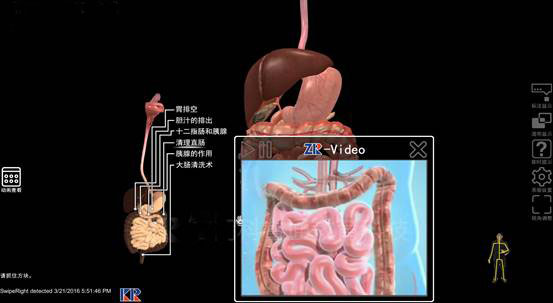

數(shù)字人(rén)體(tǐ)體(tǐ)感互動系統使用(yòng)3D體(tǐ)感攝影(yǐng)機(jī),借助紅(hóng)外(wài)線識别人(ré€n)體(tǐ)的(de)運動,追蹤全身(shēn)動作(zuò),根據掃描數(shù)據,建立數(shù)位骨架&。通(tōng)過大(dà)量的(de)标本影(yǐng)像文(wén)本、圖形、動畫(huà)、聲音(yīn)、視(↓shì)頻(pín)等多(duō)種媒體(tǐ)信息,使抽象、靜(jìng)态、枯燥的(de)理(lǐ)論知(zhī)識變得(de)直觀形象、生(¥shēng)動活潑。使教學由平面走向立體(tǐ),化(huà)抽象為(wèi)具體(tǐ),使學生(shēng)♣在輕松愉悅中接受教育,并激發學生(shēng)的(de)學習(xí)積極性和(hé)主動性,達到(dào)“以學生(shēng)自(zì)學為(wèi)主體(tǐ),教師(shī)指導為(wèi)輔®助”的(de)翻轉課堂的(de)目标。

(1) 科(kē)技(jì)化(huà)、趣味化(huà)相(xiàng)結合的(de)©教學模式 應用(yòng)虛拟現(xiàn)實技(jì)術(shù)來(lái)呈現(xiàn)人(rén)體(tǐ)內(nèi)部組織結構,€同時(shí)引入多(duō)種學習(xí)模式來(lái)激發學生(shēng)的(de)學習(xí)興趣。學生Ω(shēng)可(kě)根據自(zì)己喜愛(ài)的(de)學習(xí)時(shí)間(jiān)、學習(xí)環境。在課前就(jiù)進行(xí★ng)部分(fēn)知(zhī)識點學習(xí),在課堂上(shàng)的(de)實踐學習(xí)中快(kuài)速吸收教學內(nèi)容,并在課後可(kě)針對φ(duì)自(zì)己的(de)薄弱環節再次進行(xíng)實訓學習(xí),以達到(dào)科(kē)技(jì)化(huà)、趣味化(huà)相(xiàng)結合的(de)×學習(xí)目的(de)。